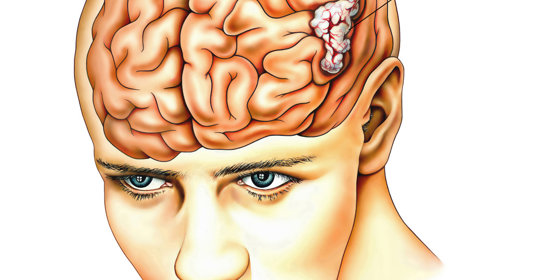

大腦與神經

神經麻痺困擾中:瞭解成因與有效康復策略!

腦溝變寬揭秘:症狀、原因及現代醫學治療全面解析!

腦實質出血:應對急救和康復的實用指南!

腦功能不全怎麼辦?認知障礙應對指南大揭秘!

腦水腫症狀辨析:正確認識問題,尋找治療方案!

劇烈頭痛:頭部的急救信號,症狀及科學調理方法詳解